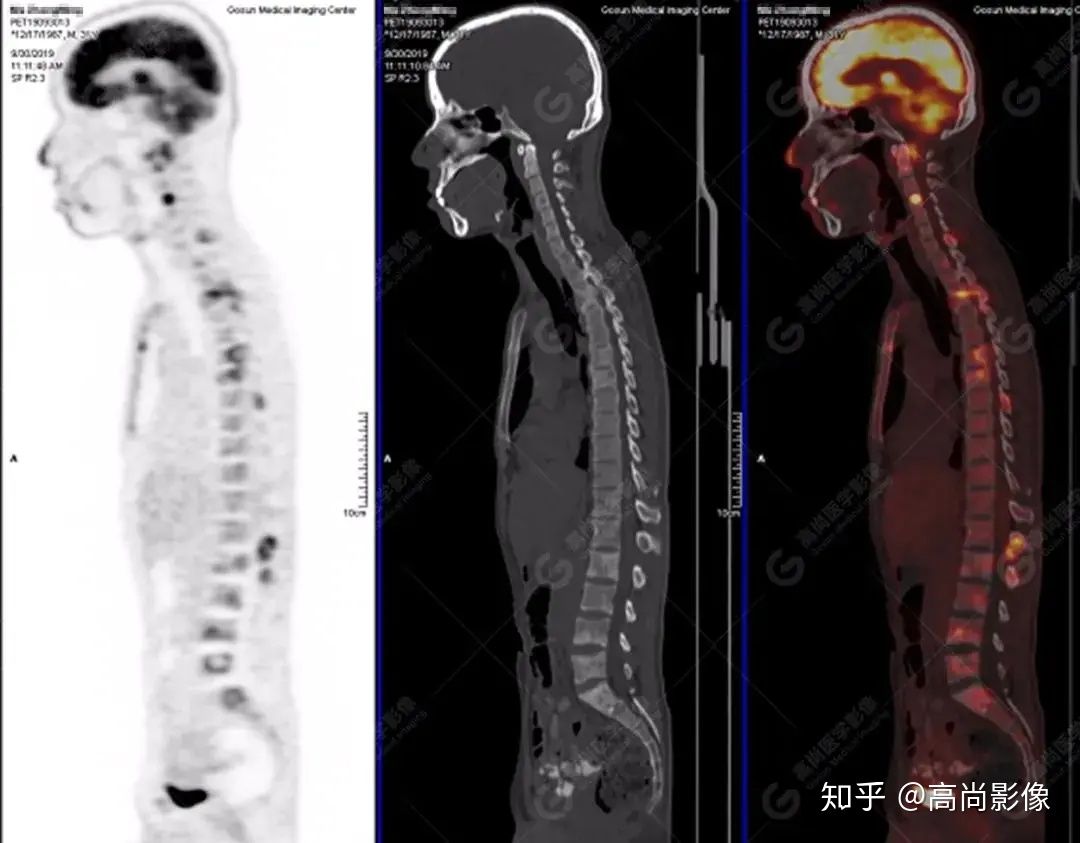

脊柱多發(fā)椎體及附件骨質(zhì)破壞,代謝不均性增高

【PET/CT提示】雙肺、左側(cè)胸膜多發(fā)結(jié)節(jié)影,全身多處骨質(zhì)破壞,全身多發(fā)淋巴結(jié)腫大,代謝攝取不均勻性增高。

2.全身多系統(tǒng)、多形態(tài)、多發(fā)病灶(肺部、胸膜、淋巴結(jié)、骨),18F-FDG攝取不均性增高;

特征:肺部病灶簇狀分布,上葉尖段及下葉背段為著;腫大淋巴結(jié)分布不對(duì)稱,無(wú)融合、中央有壞死改變,與淋巴瘤、轉(zhuǎn)移瘤等有一定的鑒別診斷意義;